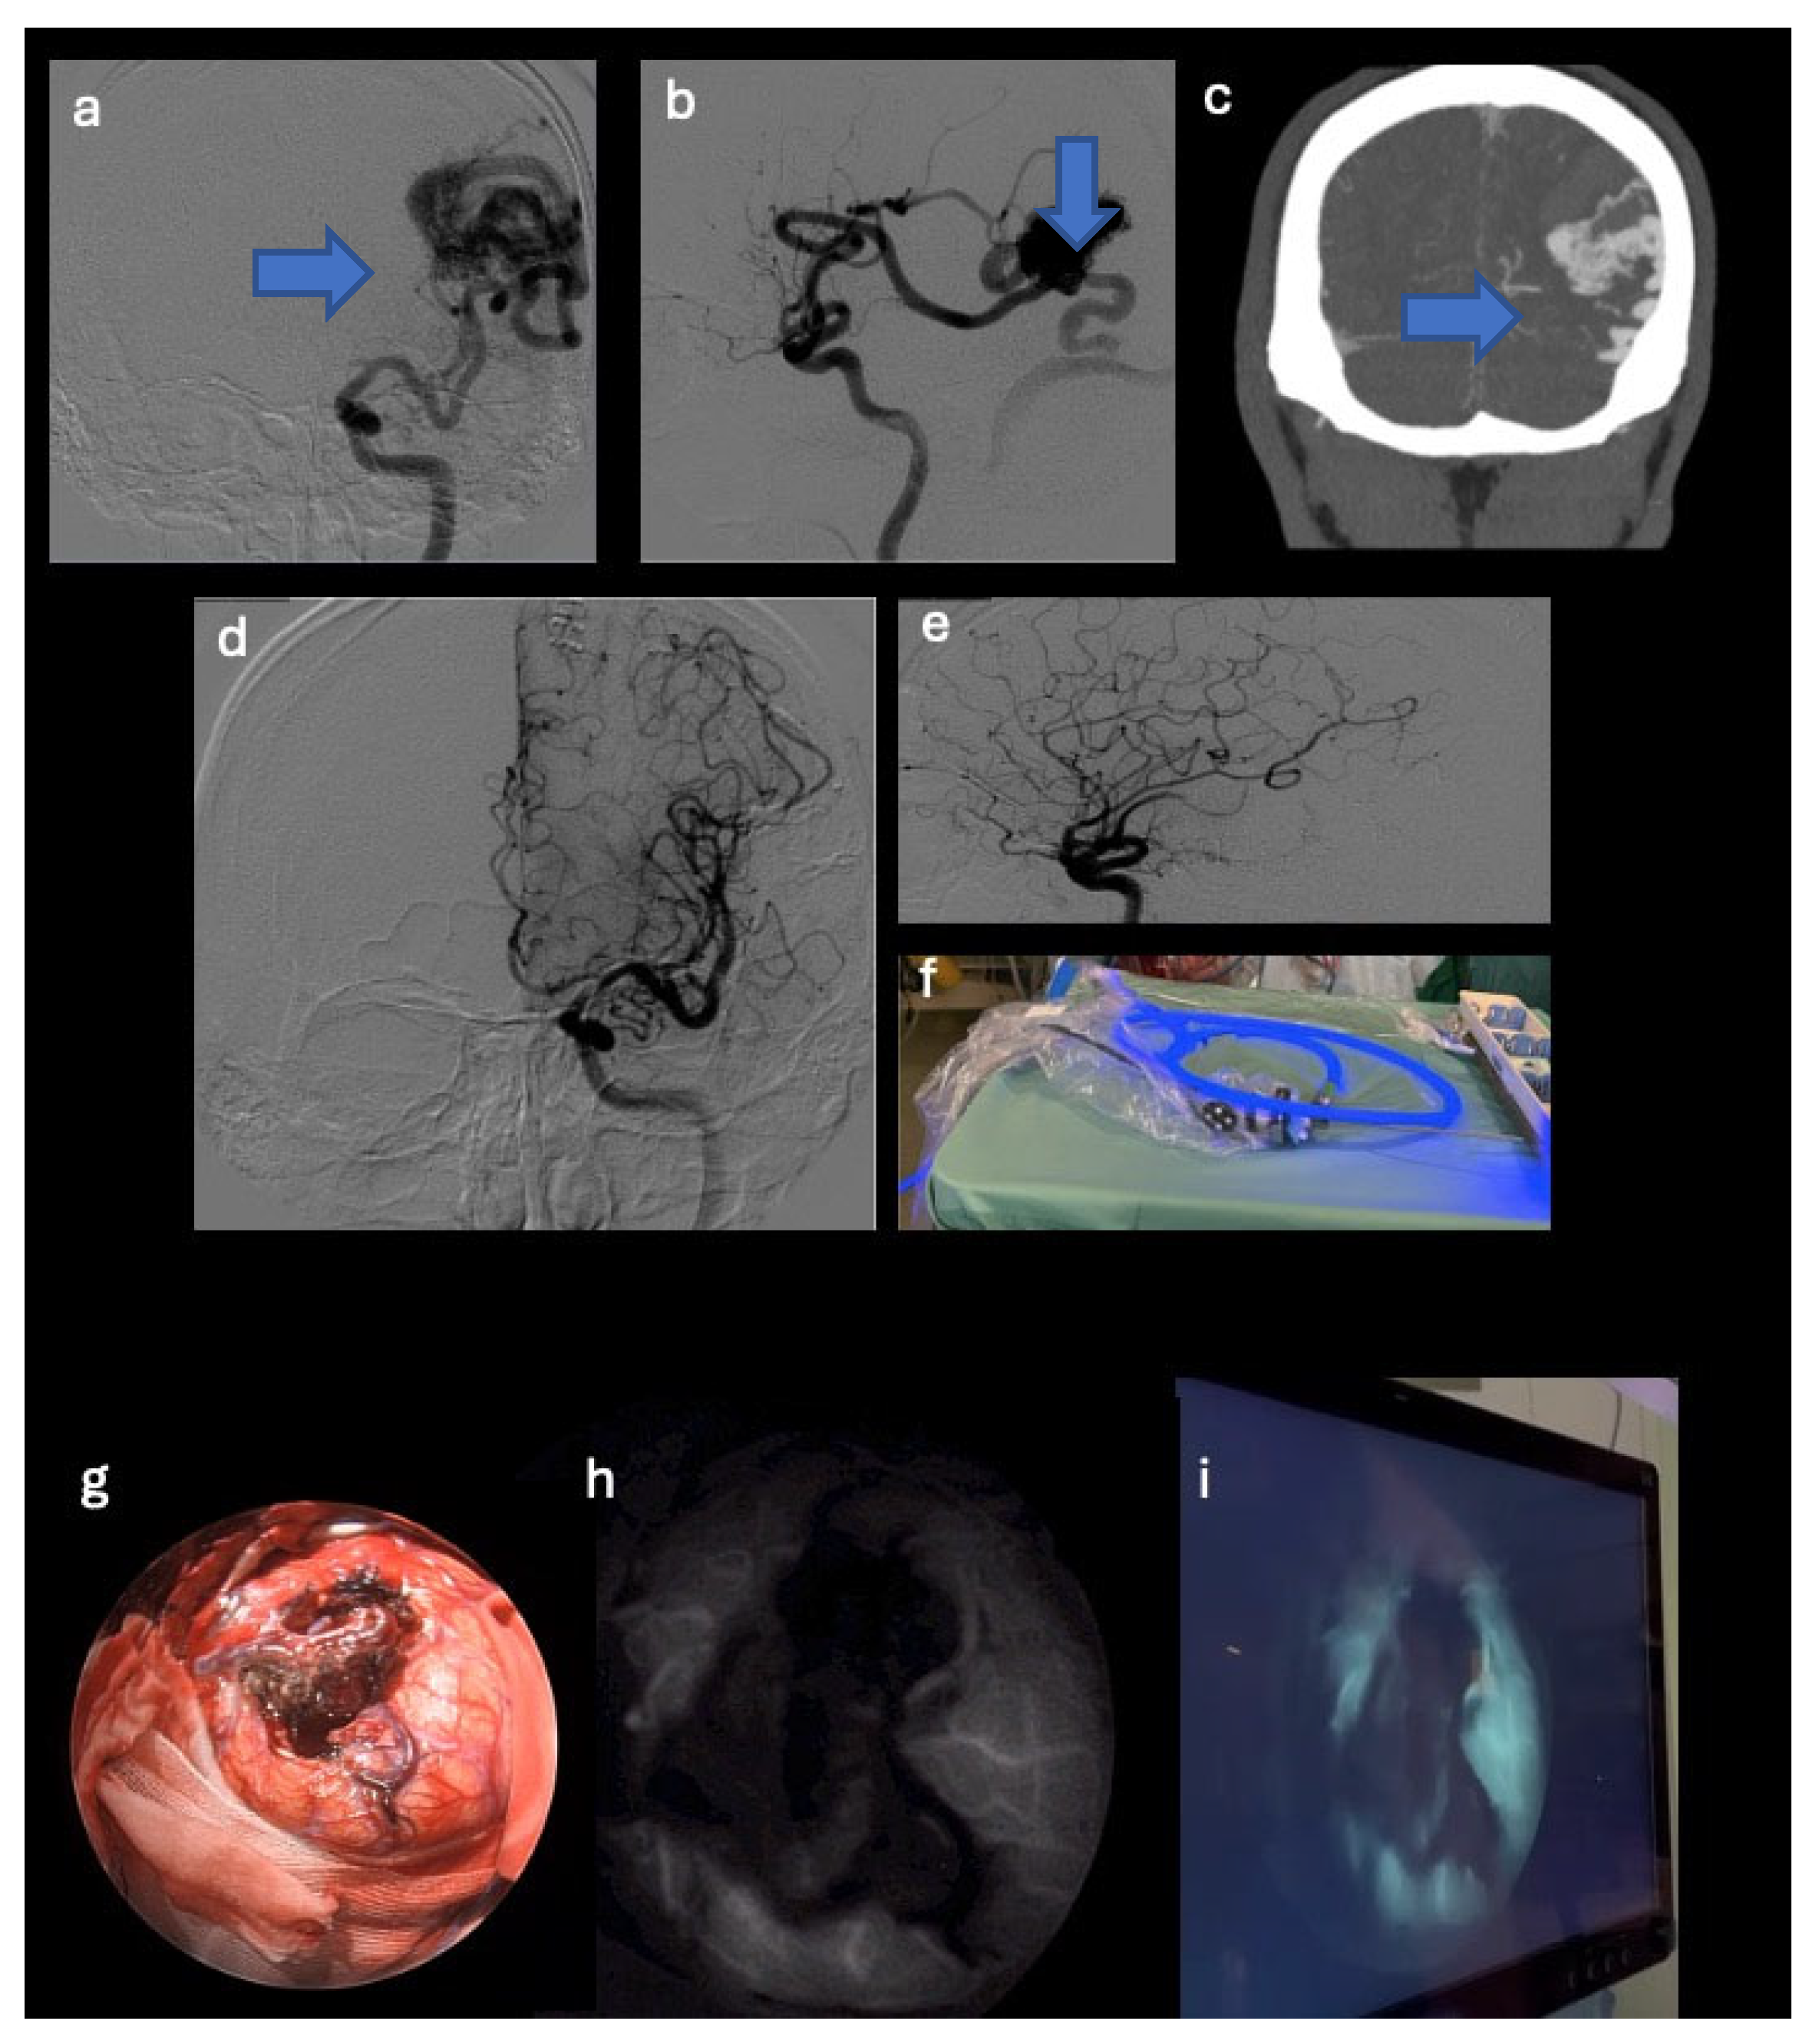

- A 73-year-old female patient with temporal AVM originating from the left middle cerebral artery and discharge into the ipsilateral transverse sinus, with a 3 cm nidus. The AVM manifested itself with an episode of fluent aphasia. The patient underwent preoperative embolization and microsurgical removal of the nidus (see Figure 1).

3.2.1. Case Number 2

| 2 | 73 | F | Episode of fluent aphasia | Left temporal AVM originating from the left middle cerebral artery and venous drainage into the ipsilateral transverse sinus (3 cm nidus) | Preoperative embolization and the microsurgical removal of the nidus | Complete removal of the nidus and transient fluent aphasia lasting three months; no bleeding events. |